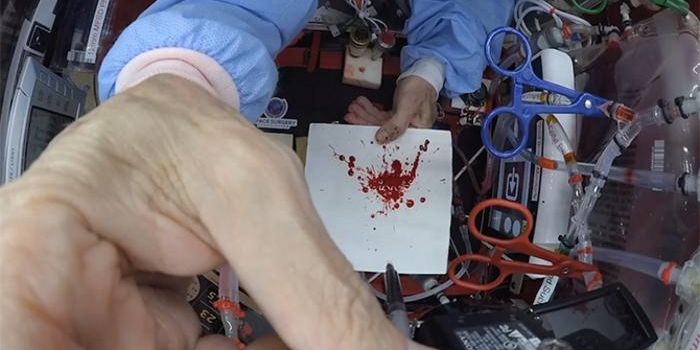

SEP 09, 2024Space & AstronomyHow can microgravity help advance cancer research? This is what an upcoming grant-awarded project sponsored by the Inter ...

AUG 20, 2024Space & AstronomyThe International Space Station (ISS) has been a beacon of scientific and medical research ever since the station’ ...